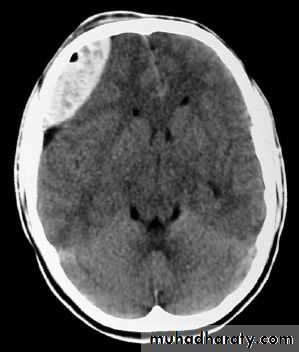

a. Extradural Haematoma

Usually due to TRIVIAL trauma.Source of bleeding(Haematoma):

1. Linear squamous temporal skull fractures with laceration of a branch of the underlying middle meningeal artery.2. Fractured bone edges.

3. Laceration of the dural sinuses.

CT scan will show biconvex or lens configuration.

They are more likely to occur in the younger age group.

An extradural haematoma is a neurosurgical emergency.

Surgical treatment by evacuation of haematoma via CRANIOTOMY.

Care must be taken in assessing patients with linear fractures crossing the middle meningeal territory.